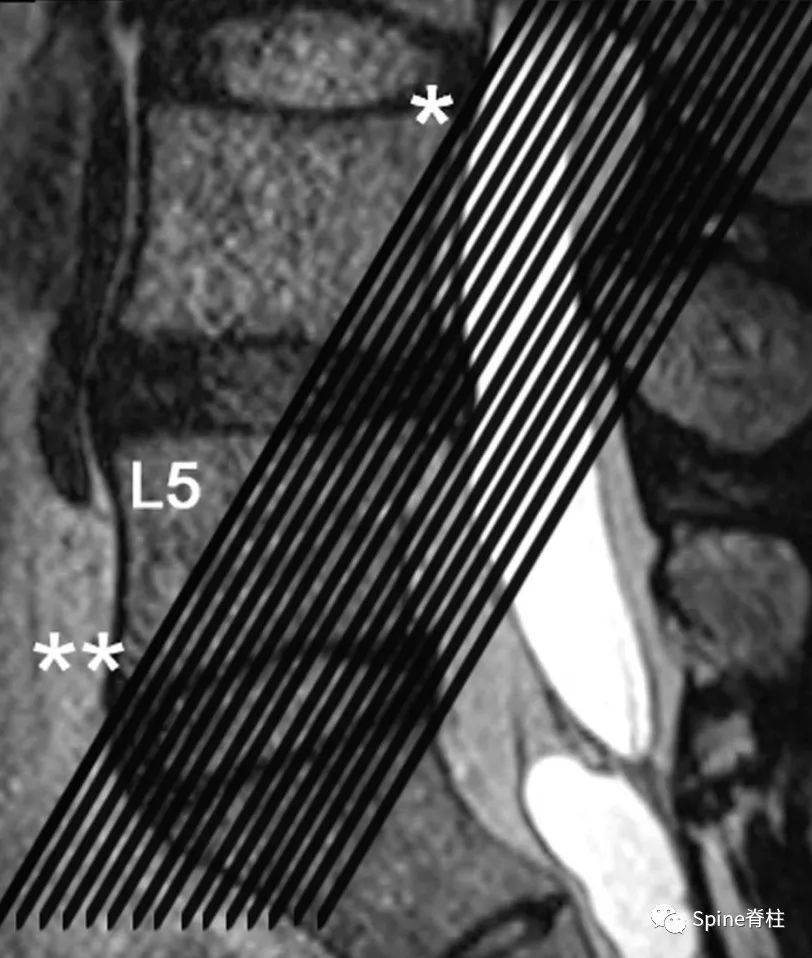

图示:通过T2加权像(T2WI)矢状位显示的斜冠状位T2WI切取的图像。黑线通过L4椎体的上后壁(*)和L5椎体的下前壁(**)。